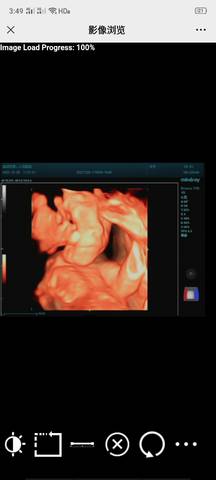

猜猜看是男宝女宝有没有B超眼????

看不出来,这个单上的数据是很难直接判断男孩还是女孩的哦,其实只要孩子健健康康就好,生下来才最准

通过这些是看不出来的,而且也不准确,在怀孕期间,我觉得只要宝宝发育好的话,还是不要想太多了,男孩女孩都一样的。

你好,我们都是一样觉得好奇,确实没什么依据,就个惊喜给自己吧,一切顺利!

你好。我们是判断不了男宝宝跟女宝宝的,孕期定期检查,我觉得宝宝健康就好的。祝心想事成 。

亲爱的,通过这些判断不出来是什么样性别的哈,反正宝宝发育好就是最好的哈,祝你好孕。